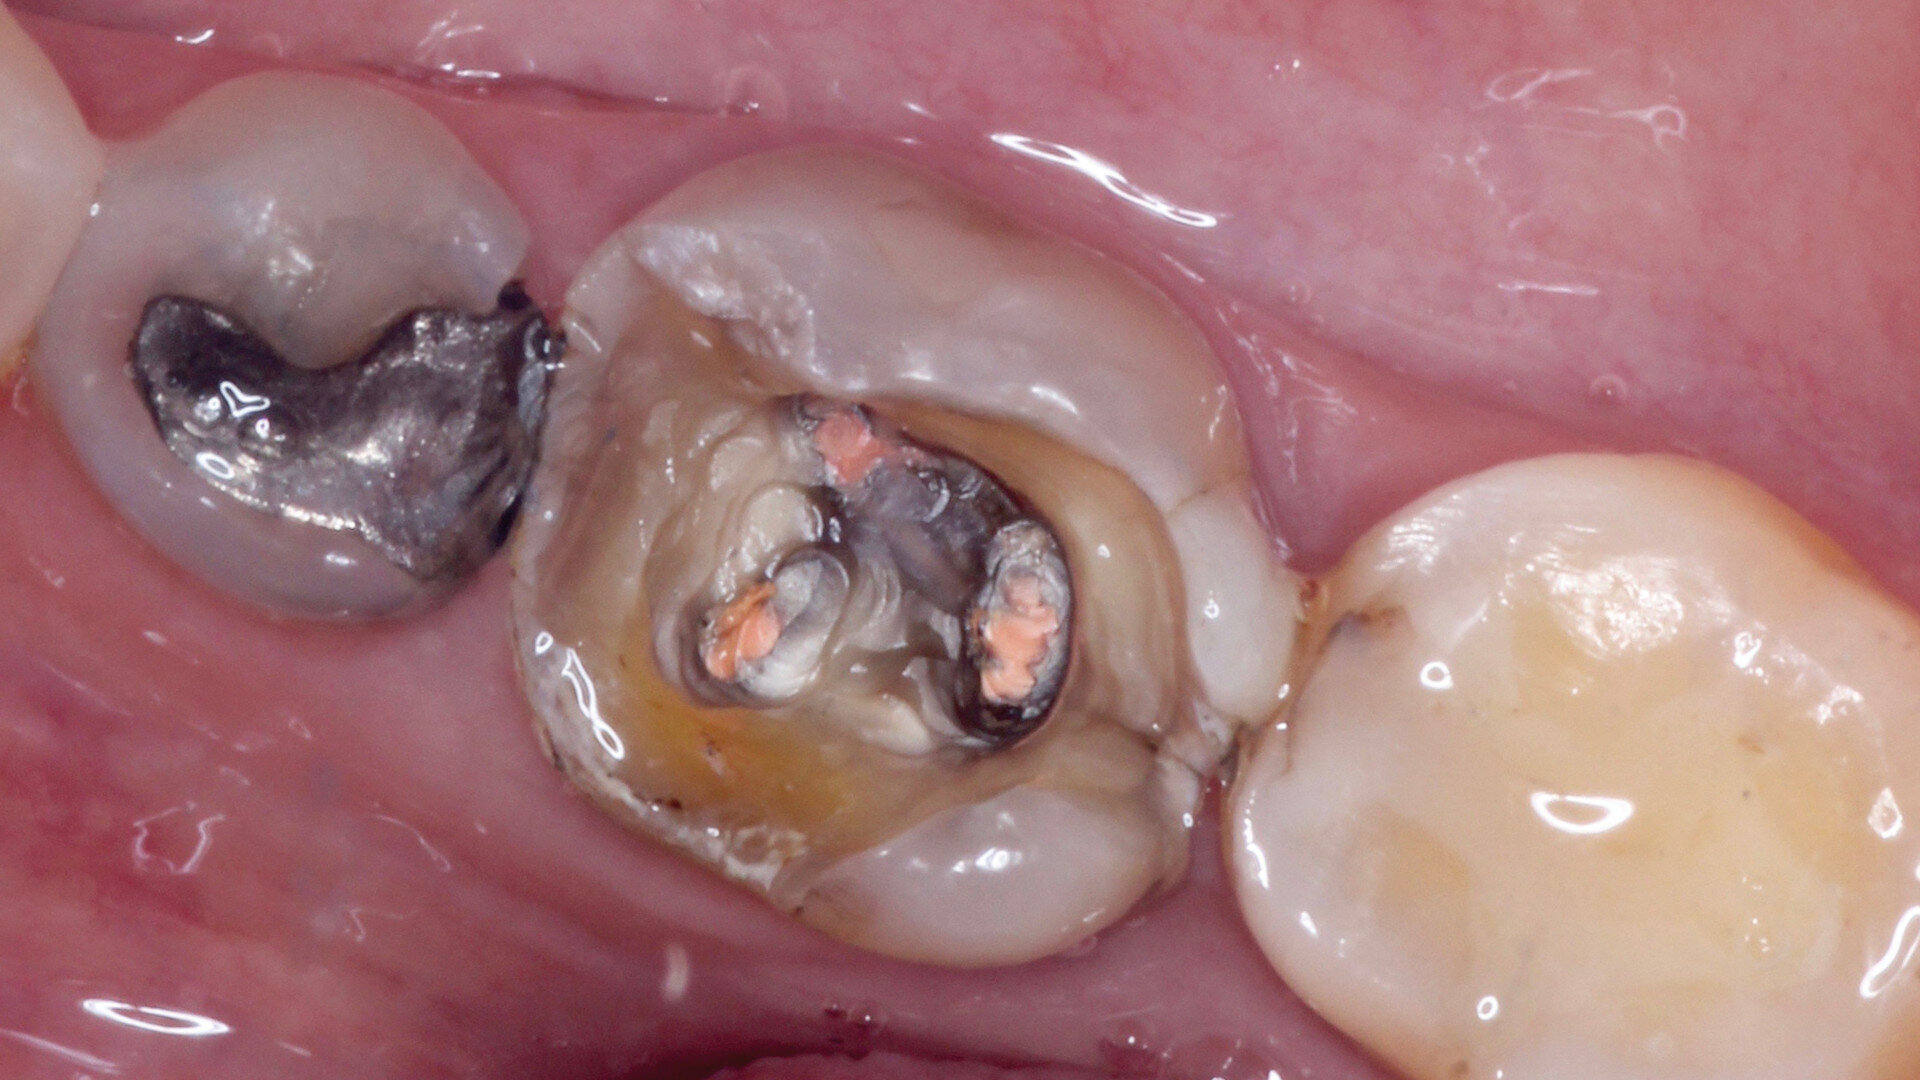

Fig. 6: Occlusal view of the pulp chamber and cavity after preparation for the milled endocrown.

For the endocrown on tooth #46, we first revised the pulp chamber using ultrasonic tips (Helse Ultrasonic) and then the tooth cavity with various rotary instruments. We performed minimal shoulder preparation in accordance with the conventional rules for ceramic restorations, avoiding undercuts and preserving minimum thicknesses (Fig. 6). An intra-oral scan of the revised surfaces was performed with the TRIOS intra-oral scanner (3Shape; Fig. 7). After that, a temporary filling with Clip F (VOCO) was prepared for the time needed for chairside manufacture of the indirect restoration (Fig. 8).